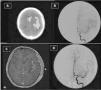

Aneurisma distal de la arteria cerebral media izquierda localizado con neuronavegación durante la cirugía

M. Rivero-Garvía, G.R. Boto, A. Pérez-Zamarrón, R. Gutiérrez-González

Hospital Clínico San Carlos. Madrid. España